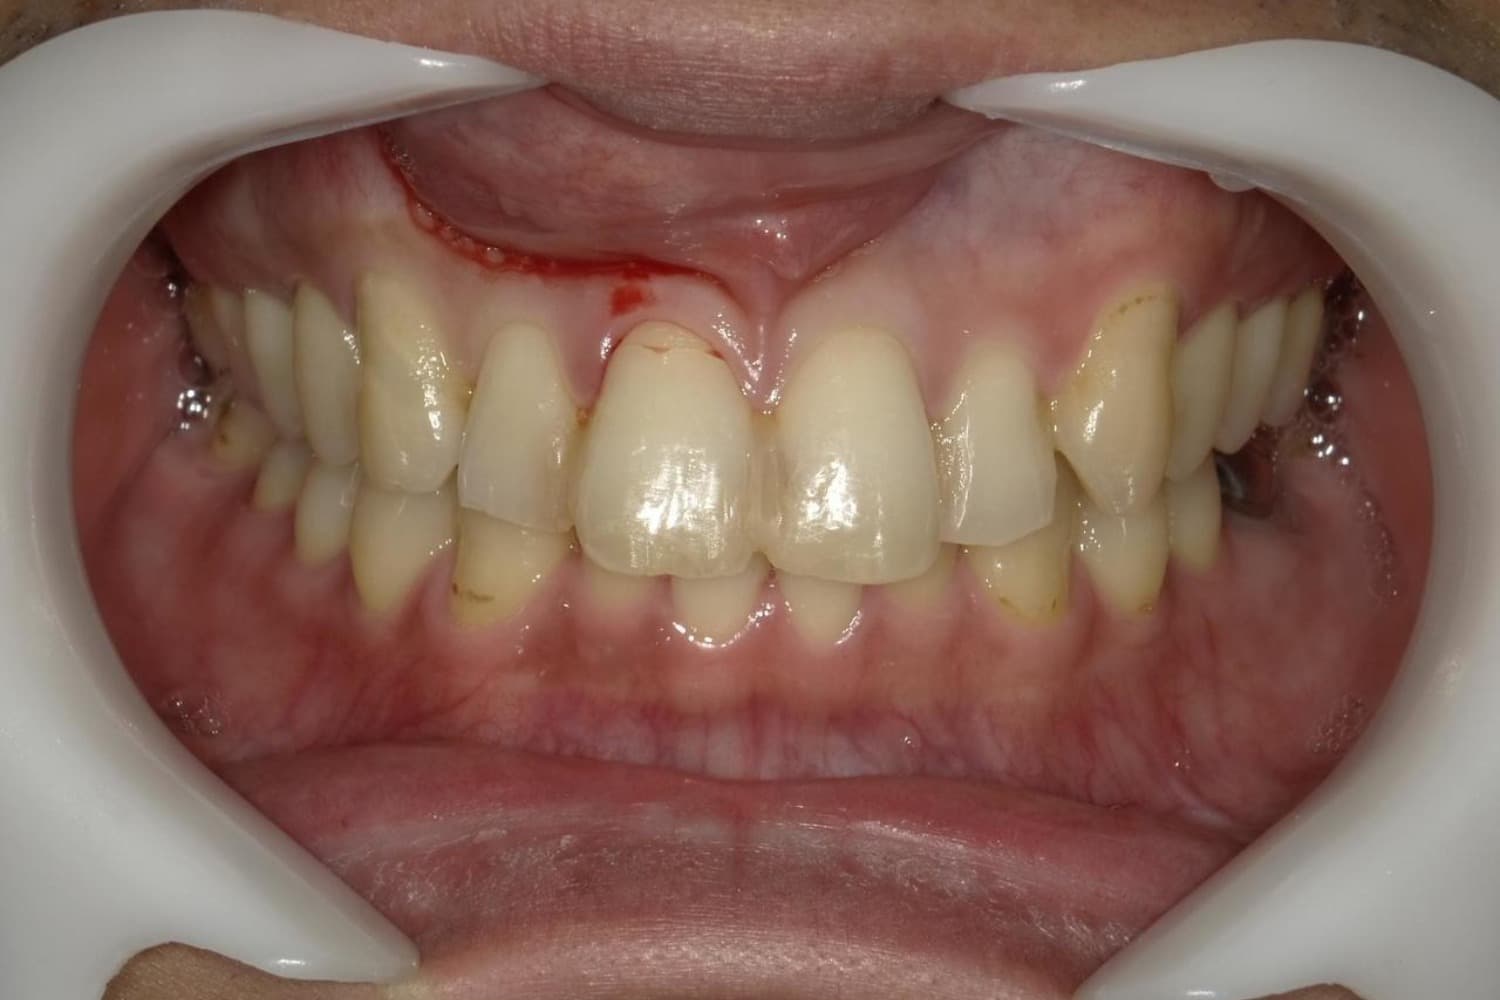

歯根破折した前歯のインプラント治療(30代男性)

After

外傷によって歯根破折した前歯を抜歯してインプラント治療をおこなう(当日に仮歯の装着までおこなう)。

年齢

30代

性別

男性

主訴

外傷によって歯根破折している。

治療期間

2ヵ月半

治療回数

6回

費用

385000円(税込) 費用の内訳: 【インプラント基本料】330000円(税込み) 基本料金に以下を含む ・フィックスチャー及び手術費用 ・投薬費用、 ・レントゲン費用 ・インプラント上部費用(アバットメントおよびジルコニアクラウンの費用用) 【オプション費用】 ・抜歯即時埋入・即時負荷加算(プロビショナルレストレーション費用・人工骨費用・暫間アバットメント費用・抜歯費用を含む)55000円(税込)

副作用・リスク

・手術後に痛み・腫れ・出血・合併症等を引き起こす恐れがあります。 ・噛む感覚がご自身の歯と異なることがあります。 ・見た目がご自身の歯と異なる場合があります。 ・手術後もメインテナンスを続けないと、インプラントが抜け落ちてしまう恐れがあります。